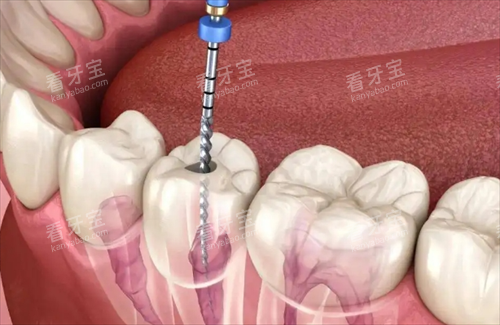

采用靠前的种植技术,能够为缺失牙齿的患者提供稳定、美观的种植牙解决方案。

在种植过程中,在意手术的安心性和更准一些性,减少患者的痛苦。

在种植过程中,采用智能化导板技术更准一些定位,配合CBCT三维扫描确定种植角度,有效避免神经损伤风险。